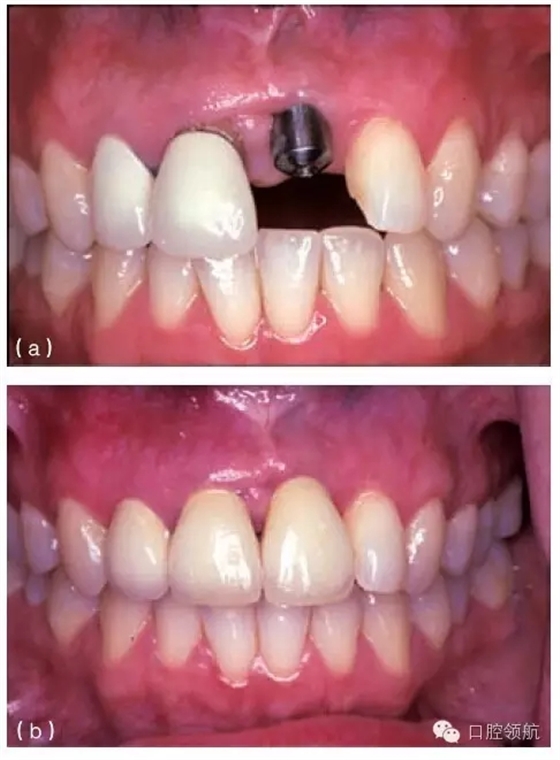

其他的美學(xué)問題與種植體植入位置不當(dāng)(圖10.20a,b),以及植入前存在骨吸收有關(guān)。骨吸收的存在使種植體無法植入到理想位置,造成單冠之間或是固定局部義齒的橋體之間存在頸部間隙(圖10.21)。

圖10.20 (a)中切牙種植體的位置太偏唇側(cè),采用定制的基臺(tái)盡可能補(bǔ)償頰側(cè)的錯(cuò)位。(b)一并更換相鄰的兩個(gè)冠修復(fù)體以獲得更滿意的結(jié)果。

種植體植入太偏唇側(cè),將造成明顯的美學(xué)問題,而且通常很難克服(圖10.20a,b)。